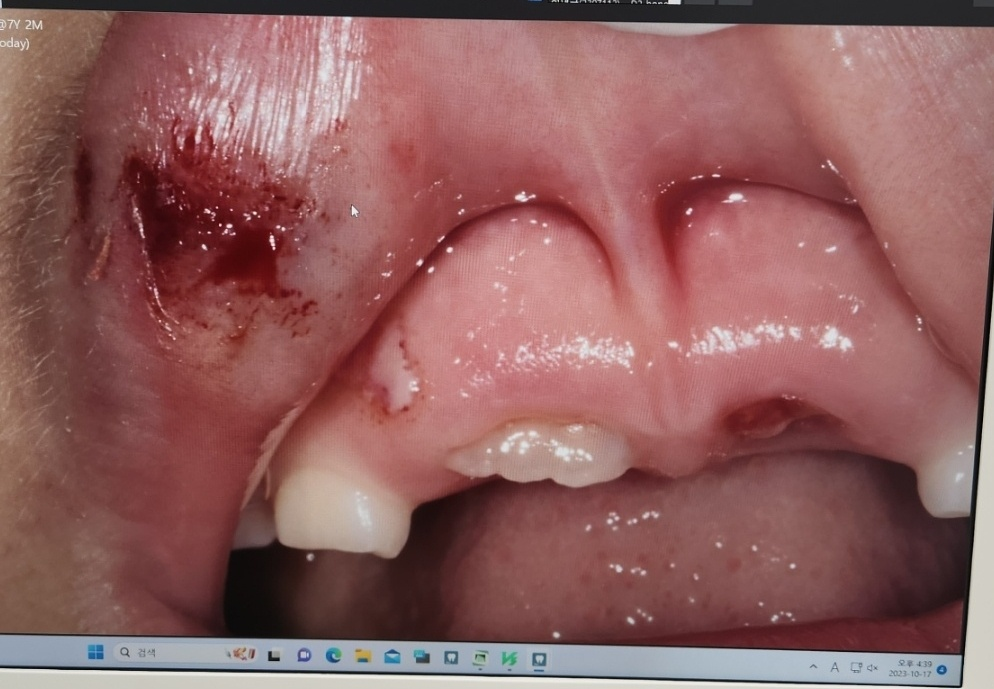

아이 입이 다쳤었는데..지금이라도 성형외과를 가봐야 할까요?

8살아이 친구한테 맞아서 다쳤어요

10월 17일날 치과에서 찍은 사진이구요

지금 3주가 지났는데 겉으로 보기에는 티가 잘 안나는데..

아이가 며칠전부터 계속 다친쪽 입을 만지면서. 엄마 여기가 이상하다고 해서 만져봤더니 다쳤던 부위가 매끄럽지 않고 툭 튀어 나왔어요

문제는 아이가 이부분을 만지면 아파해요

이미 기간이 상당히 경과한 상태이며 회복 과정에서 보일 수 있는 소견일 것으로 사료됩니다. 병원에서 딱히 해줄 수 있는게 있어 보이지는 않습니다만 혹시 걱정되고 상태를 제대로 평가받기 희망하신다면 성형외과 진료를 받아보시는 것도 좋은 생각이긴 합니다.

수상으로 인해 안쪽에 혈종이 잡혔을 가능성이 있겠습니다. 대부분은 자연스럽게 호전이 되나 현단계에서 추가적으로 조치를 할 것이 있는지 성형외과쪽에서 점검을 받는것은 도움이 되겠습니다.